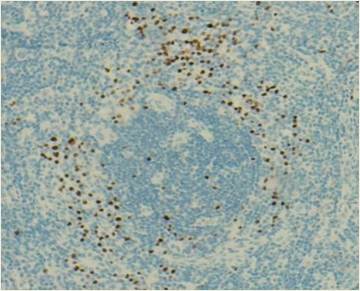

En febrero de 2019 decidió continuar el seguimiento médico de su enfermedad en nuestra institución. En dicho momento se encontraba asintomático, sin parámetros de actividad de la enfermedad y con carga viral de VHH8 no detectable. En diciembre de 2020 presentó recaída de la enfermedad con síntomas B, citopenias y valores de ferritina elevados. Se realizó una nueva biopsia escisional, en la cual se confirmó el diagnóstico mediante morfología e IHQ, evidenciando alteraciones en el tejido y células LANA-1 positivas en la zona del manto (Figuras 1 y 2). Adicionalmente, se realizaron estudios complementarios y de laboratorio para la evaluación del estado de la enfermedad. En estudios por imágenes se observaron ganglios linfáticos aumentados en zona infra y supra diafragmática, hepato-esplénicos y mediastinales. Recibió tratamiento con rituximab y doxorrubicina liposomal, logrando una segunda remisión completa.

Figura 2

Biopsia de ganglio axilar derecho. Inmunomarcación para LANA-1 (40x). Se observa positividad en células de la zona del manto. |